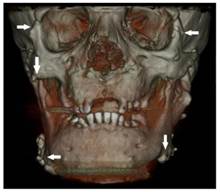

Figure 3

Osteomas at the left mandible angulus, mental protuberance and below the mandibular notch (white arrows)

Figure 4

Osteomas at the right mandible angulus and also both condyle and coronoid process deformities (black arrow)

Dental volumetric tomographic (DVT) images showed multiple osteomas of the buccal cortex of the right mandibular angle and left mandibular angle (Figure 3,4). Additionally, in the coronal and sagittal sections of the mandible condyle, a huge osteoma that limited mouth opening was diagnosed (Figure 5). Cephalometrically, he showed a slightly retrusive maxilla with an ANB angle of 1˚and a relatively normal mandibula in anterioposterior direction. His mandibular plane angle (S-N / Go-Me: 25˚) and articular angle (S-Ar-Go: 133˚) were reduced (Table 1). His profile was straight due to the slightly retruded maxilla position. According to the Steiner's S line his lips were in normal position (Figure 6). The osteomas were submitted for pathologic examination. Histopathologic examination revealed that the specimens displayed a normal-appearing dense compact lamellar bone with minimal marrow spaces and rare irregular Haversian canals that did not show osteoclasts or osteoblasts (H&E X100)(Figure 7). Due to the dental anomalies, the osteomas in the mandible and the familial history of the patient, the patient was diagnosed as GS. Following resection of the osteomas that caused discomfort, prosthetic rehabilitation was performed.